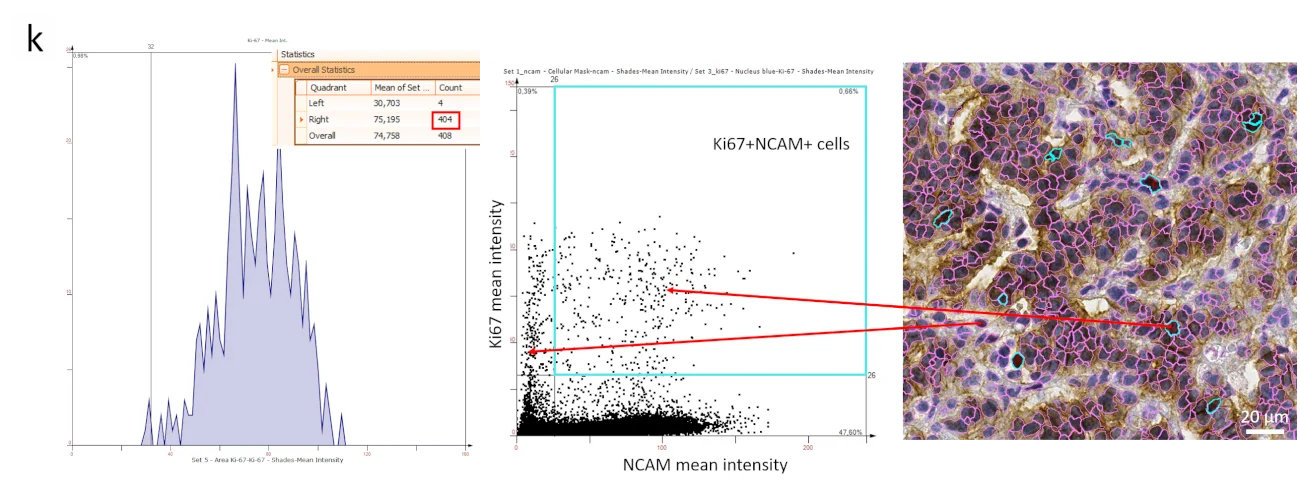

In StrataQuest, FACS-like scattergrams (k) are used to define and further segment specific cellular phenotypes. In this case study, the exact number of Ki67+ NCAM+ cells within the sample was found to be 404. The backward connection allows the visualization of double-positive cells in turquoise from the upper right quadrant or switch to Ki67+NCAM- cells in upper left.